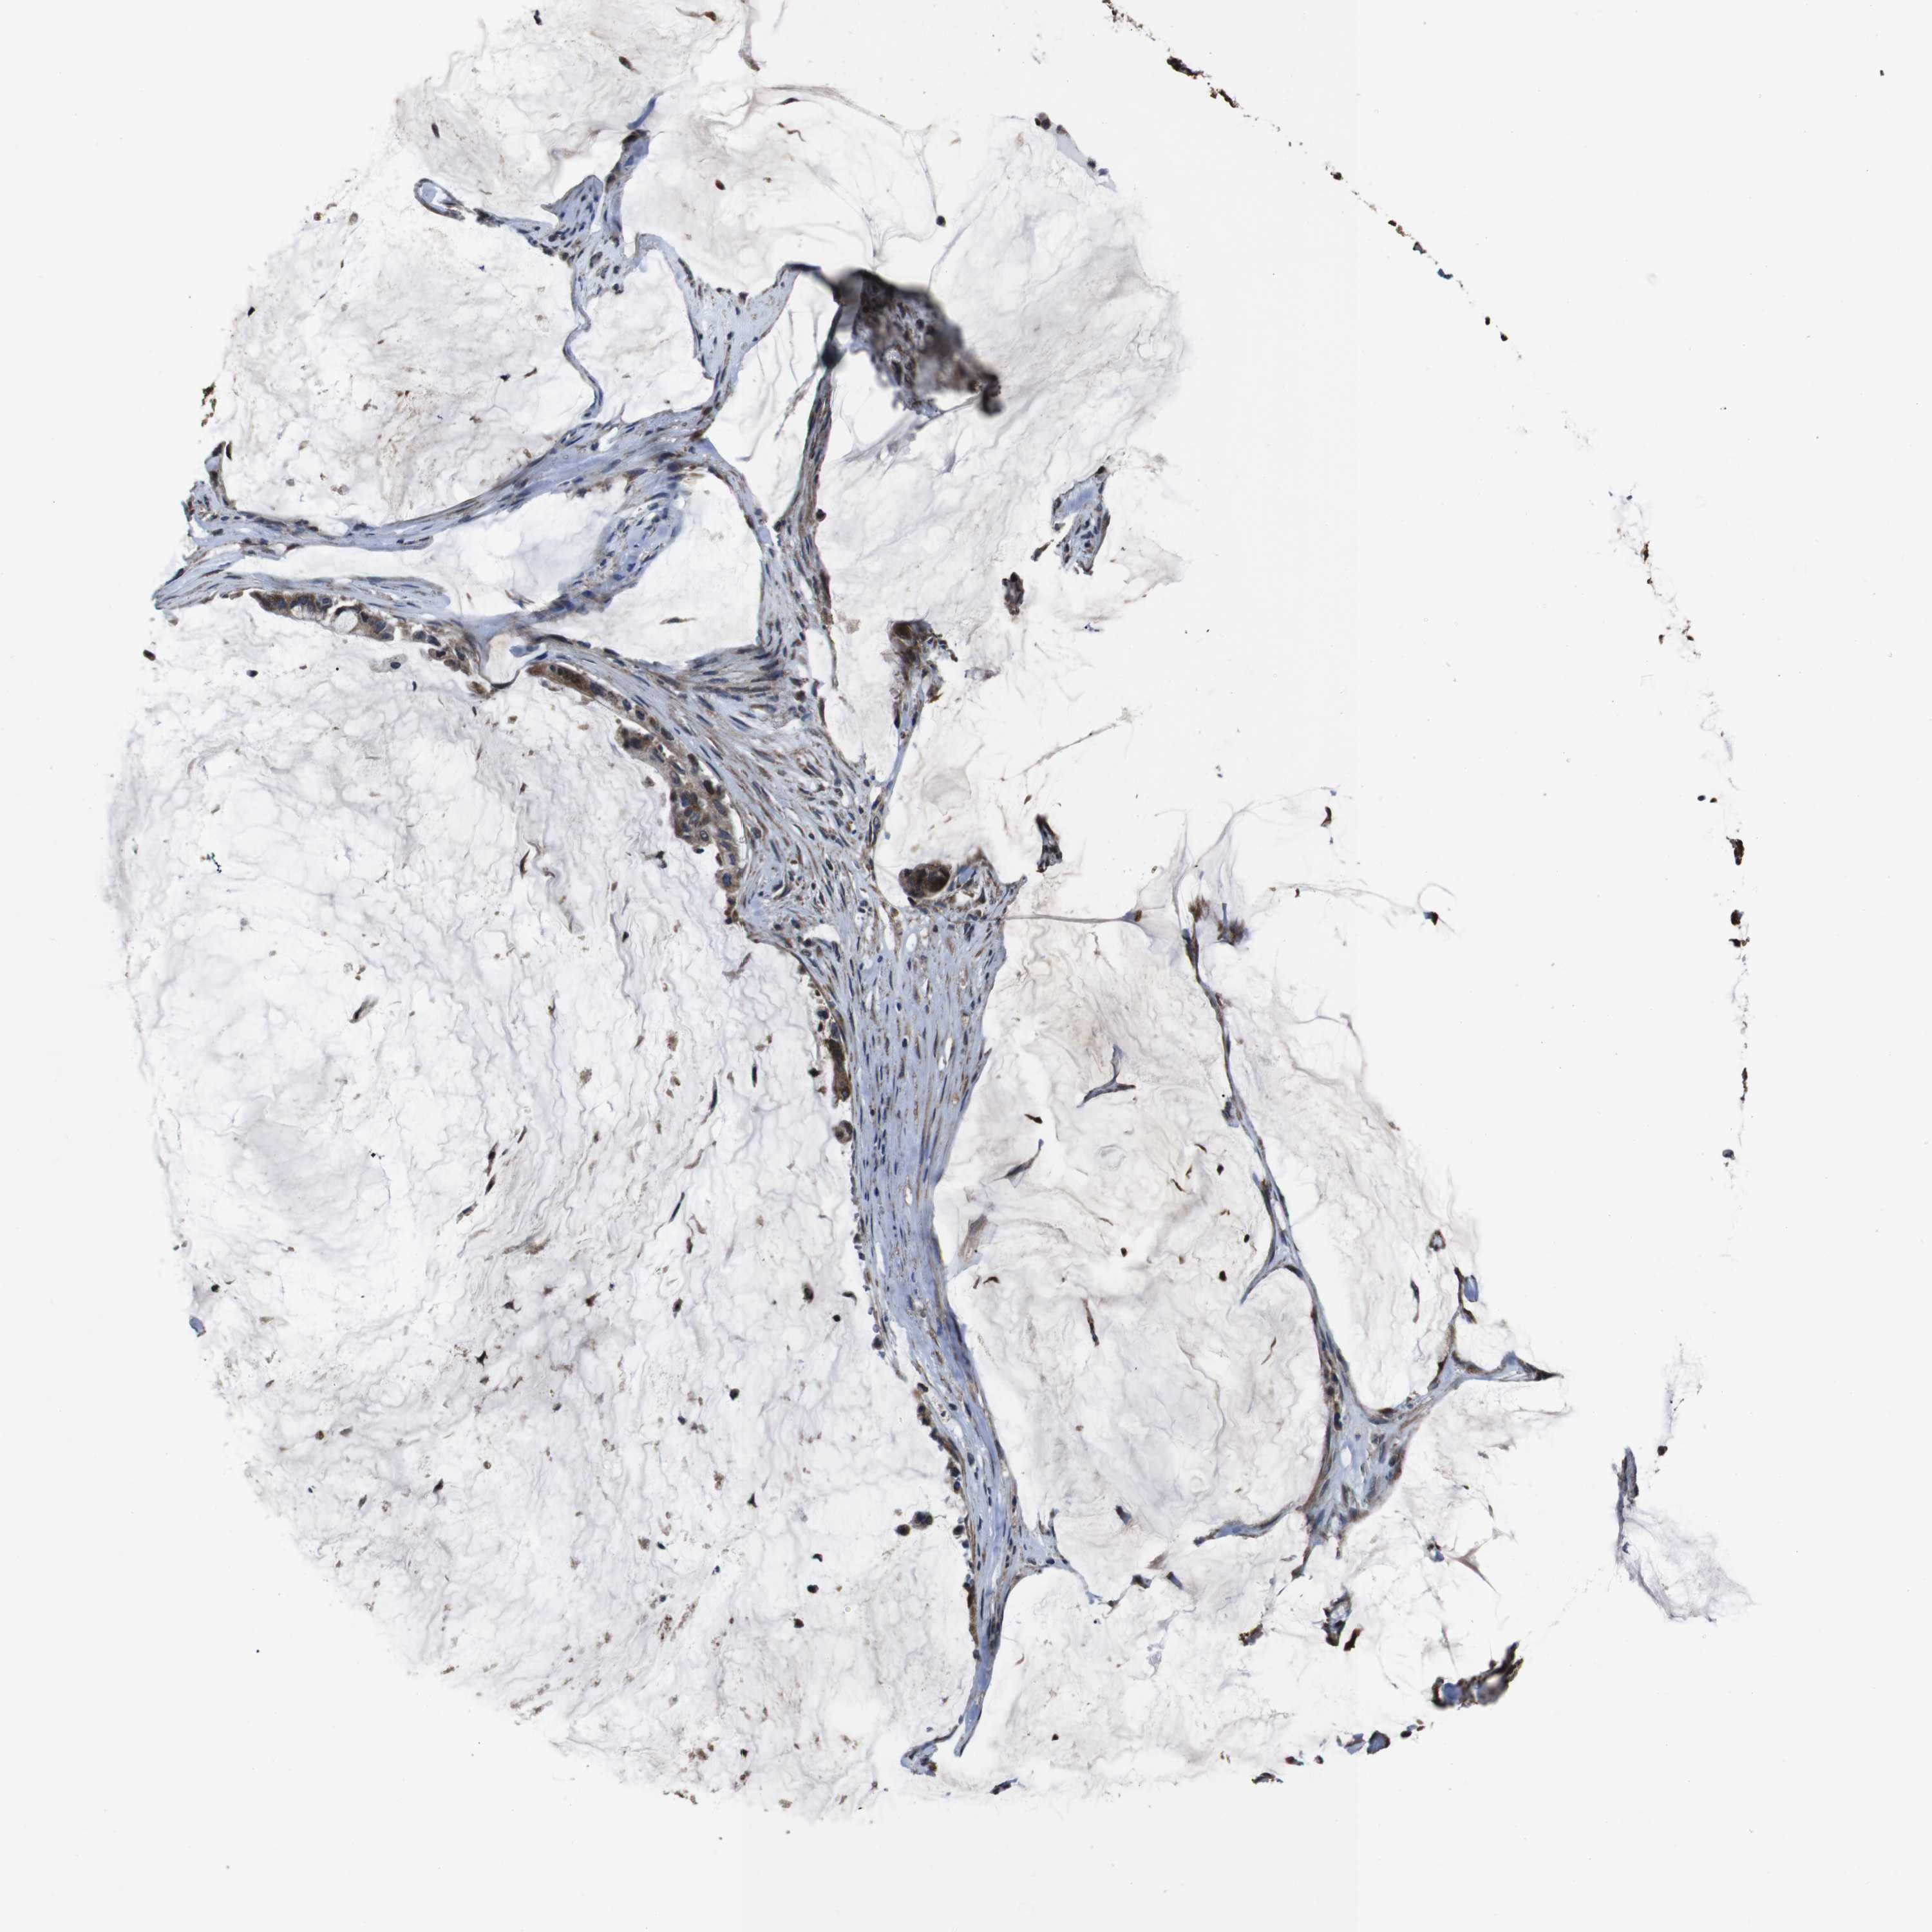

PANCREATIC CANCER - Protein expressioni

A mouse-over function shows sample information and annotation data. Click on an image to view it in a full screen mode. Samples can be filtered based on level of antibody staining by selecting one or several of the following categories: high, medium, low and not detected. The assay and annotation is described here.

Note that samples used for immunohistochemistry by the Human Protein Atlas do not correspond to samples in the TCGA dataset.

Antibody stainingi

Antibody staining in the annotated cell types in the current human tissue is reported as not detected, low, medium, or high, based on conventional immunohistochemistry profiling in selected tissues. This score is based on the combination of the staining intensity and fraction of stained cells.

Each image is clickable and will lead to virtual microscopy that enables deeper exploration of all samples and also displays staining intensity scores, fraction scores and subcellular localization as well as patient and tissue information for each sample.

Antibody HPA011055

Staining

High

Medium

Low

Not detected

Intensity

Strong

Moderate

Weak

Negative

Quantity

>75%

75%-25%

<25%

None

Location

Nuclear

Cytoplasmic/membranous

Cytoplasmic/membranous,nuclear

Adenocarcinoma, NOS